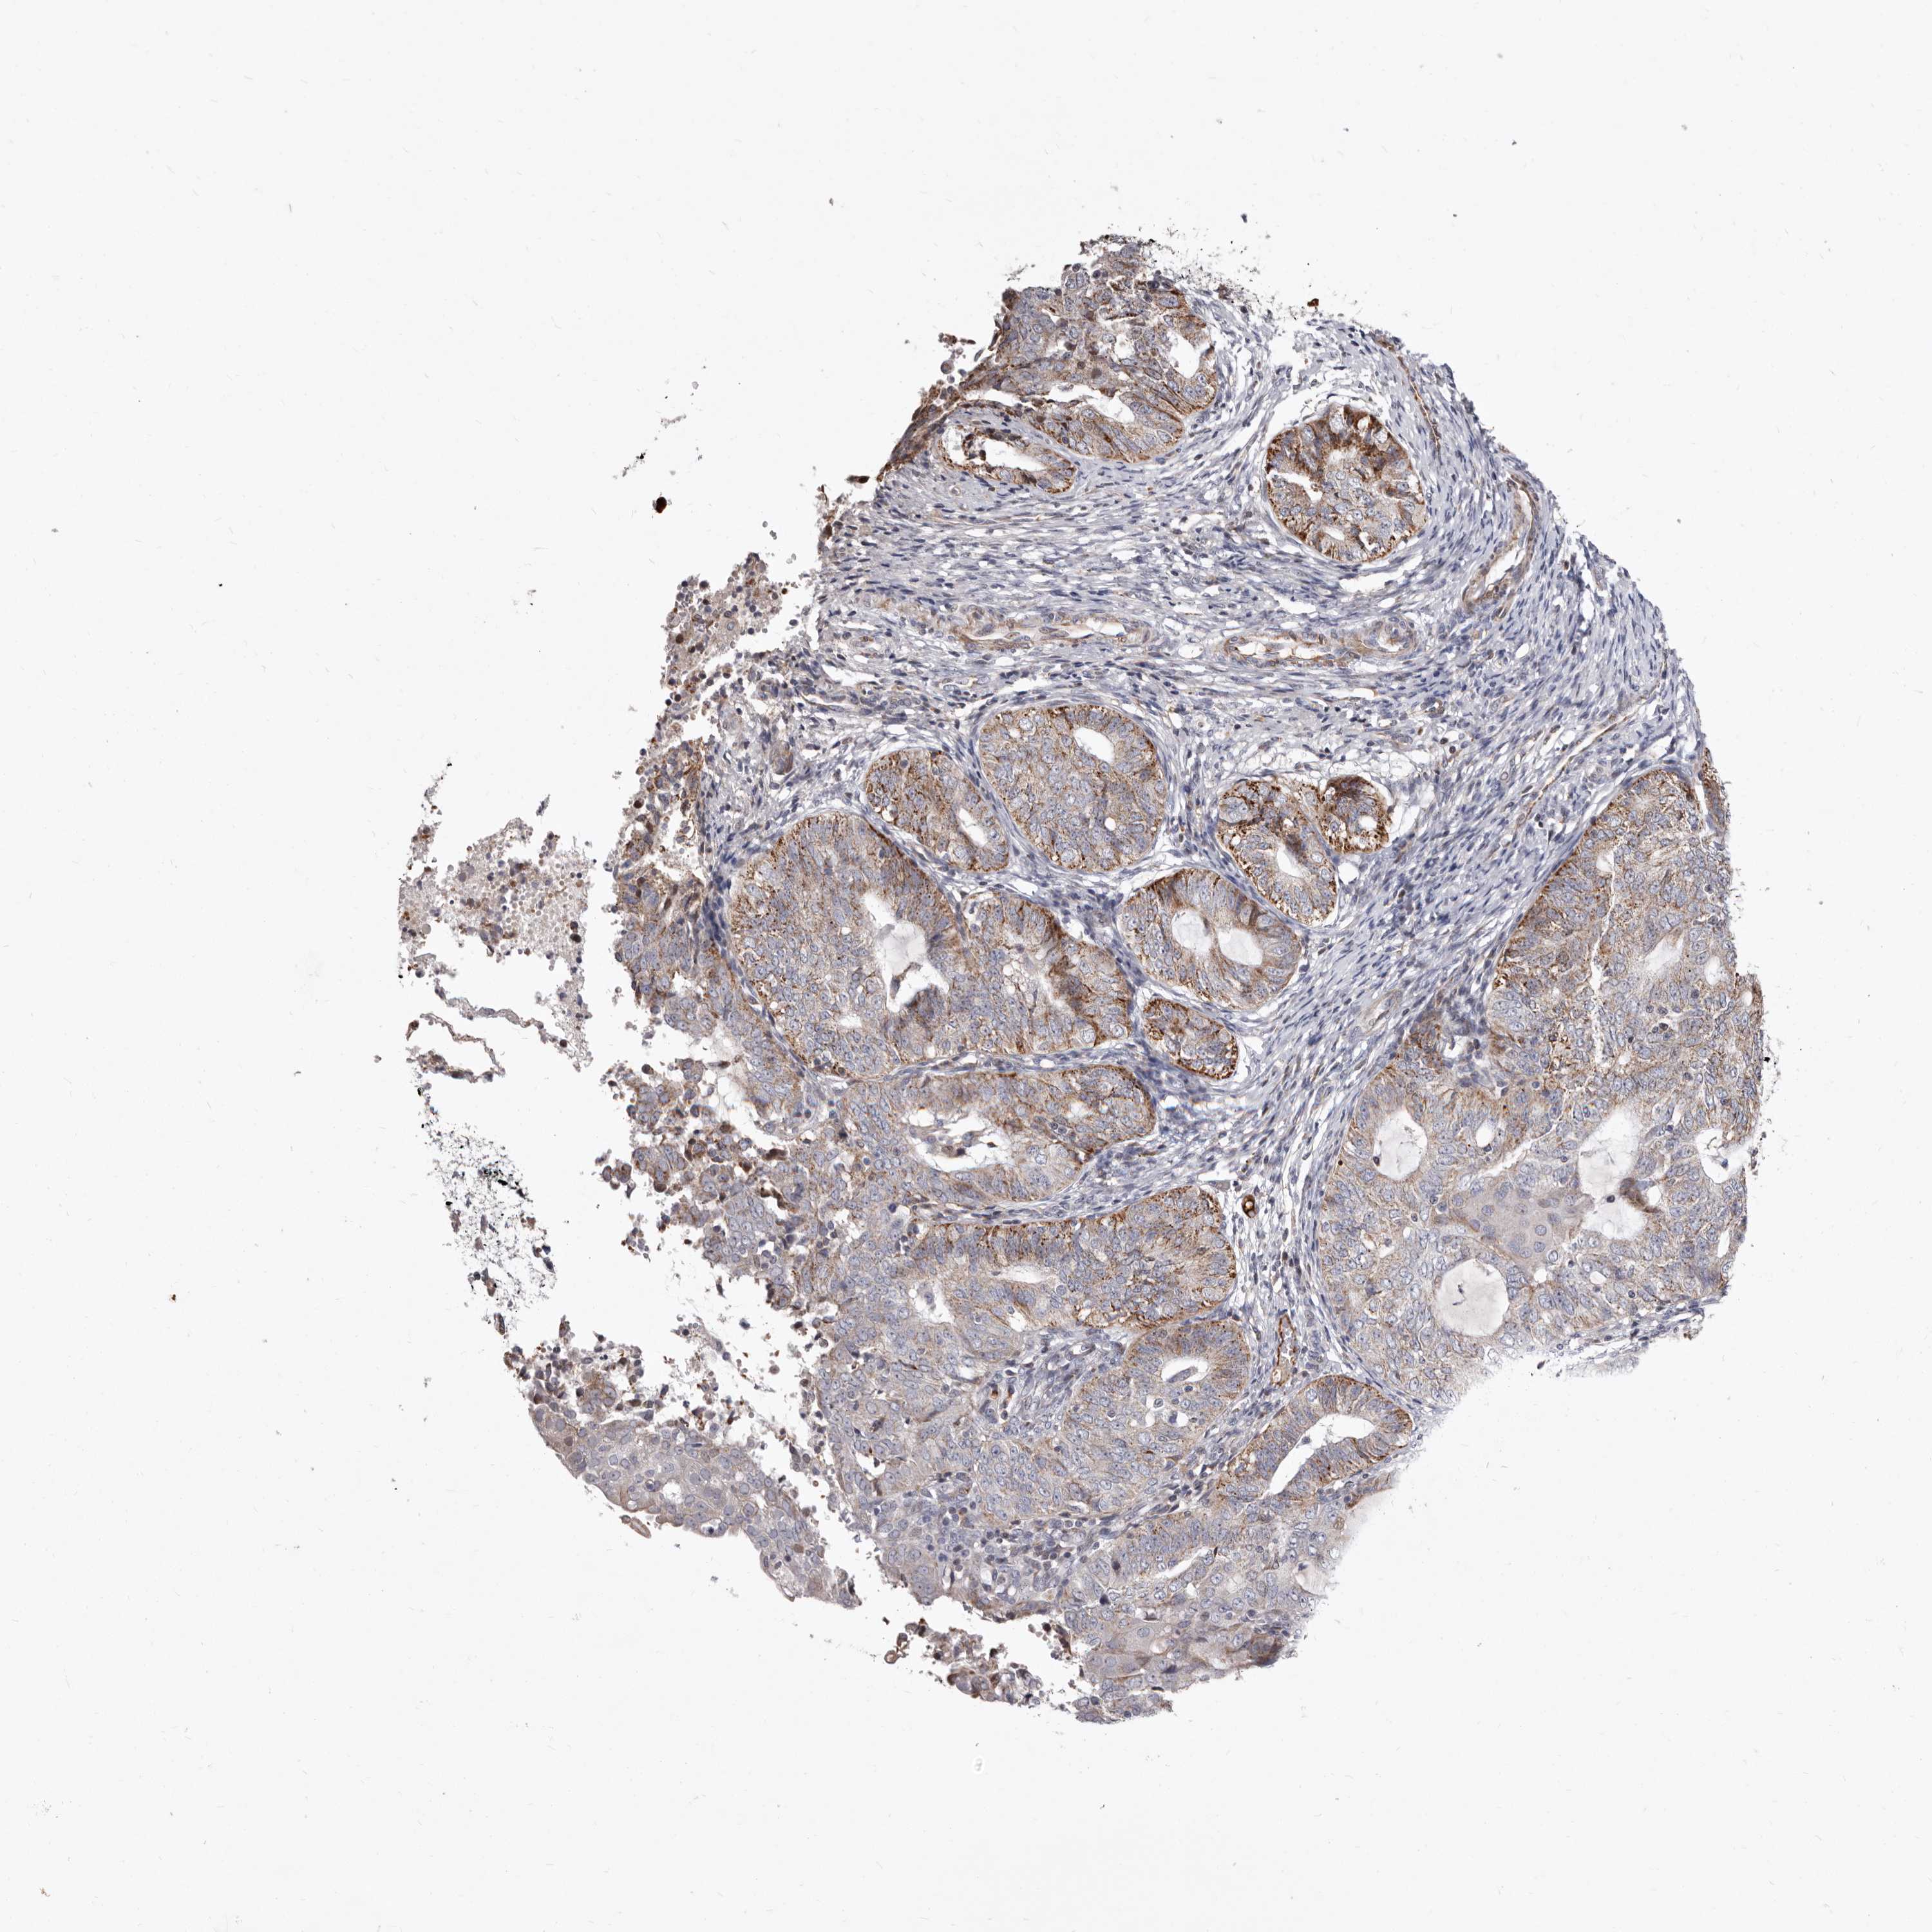

ENDOMETRIAL CANCER - Protein expressioni

A mouse-over function shows sample information and annotation data. Click on an image to view it in a full screen mode. Samples can be filtered based on level of antibody staining by selecting one or several of the following categories: high, medium, low and not detected. The assay and annotation is described here.

Note that samples used for immunohistochemistry by the Human Protein Atlas do not correspond to samples in the TCGA dataset.

Antibody stainingi

Antibody staining in the annotated cell types in the current human tissue is reported as not detected, low, medium, or high, based on conventional immunohistochemistry profiling in selected tissues. This score is based on the combination of the staining intensity and fraction of stained cells.

Each image is clickable and will lead to virtual microscopy that enables deeper exploration of all samples and also displays staining intensity scores, fraction scores and subcellular localization as well as patient and tissue information for each sample.

Antibody HPA029203

Staining

High

Medium

Low

Not detected

Intensity

Strong

Moderate

Weak

Negative

Quantity

>75%

75%-25%

<25%

None

Location

Nuclear

Cytoplasmic/membranous

Cytoplasmic/membranous,nuclear

Adenocarcinoma, NOS

Adenocarcinoma, metastatic, NOS